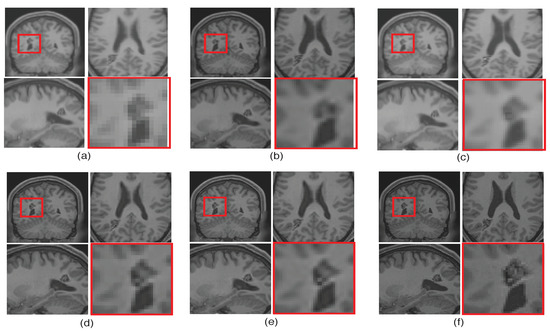

To emphasize the significance of reconstruction of uncommon image details in the proposed SR method, we chose a real MR image volume with a cavernoma and improved its resolution by factor 2, as shown in Figure 11. It can be observed that the LRTV [12] approach in Figure 11d reduces the blur as compared to interpolation and NLM3D [13] in Figure 11b,c, but tends to produce staircase effect. It can be observed that the tissue boundaries and image details inside the cavernoma, shown in the red box, are more clear and distinct for the proposed method. In addition, the skull outlines can be seen to be well defined (in the sagittal plane) in the case of the proposed algorithm (see Figure 11e) as compared to existing methods.

Figure 11.

Illustration of super resolution results for structural deformity cavernoma in real MR images, by different algorithms: (a) nearest neighbor, (b) spline interpolation, (c) non local means in three dimensions (NLM3D) [13], (d) low rank total variation based method (LRTV) [12], (e) the proposed approach, and (f) the original HR image. Each slice in axial, sagittal, and coronal planes is shown. The zoomed version of the cavernoma region from the coronal slice is highlighted in red rectangle. Please zoom for better visualization.